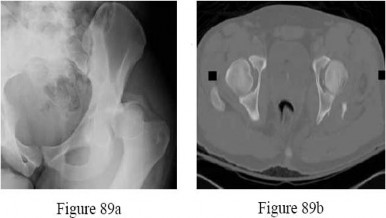

-a is the radiograph of a 24-year-old man who was involved in a motor vehicle accident. A closed reduction is performed and a post-reduction CT scan is shown in Figure 89b. What is the next most appropriate step in management?